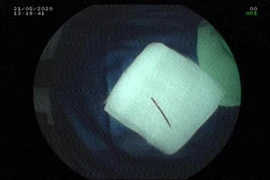

Phẫu thuật lấy ra khoảng 1kg kim loại trong bụng một bệnh nhân ảnh 1Hàng chục mảnh kim loại được lấy ra từ dạ dày của bệnh nhân. (Ảnh: TTXVN phát)

Trong 2 tiếng đồng hồ, các bác sỹ đã lấy ra khoảng 1kg kim loại (gồm các vật như đinh, thìa, bấm móng tay, thỏi sắt, móc đồ…) trong dạ dày bệnh nhân. Đáng chú ý, một số dị vật đã bị ăn mòn một phần. Sau phẫu thuật, sức khỏe bệnh nhân đã ổn định và được chuyển về Khoa Ngoại bụng để tiếp tục điều trị, theo dõi.